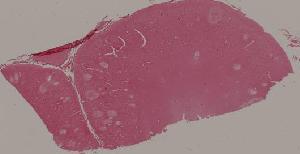

41. Opportunistic infection in the lung